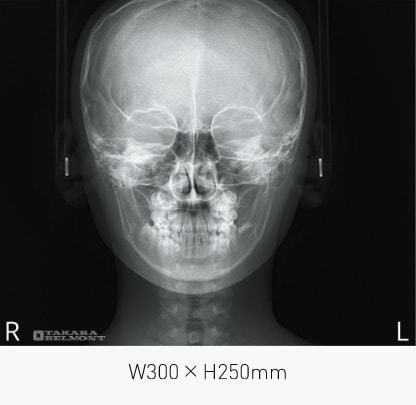

撮影モード

撮影モード

PA撮影モード

撮影仕様:セファロ

| 項目 | 内容 |

|---|---|

| 撮影部位 | 側面(LA)、正面(PA)、手根骨 |

| 撮影範囲 | W200×H250㎜ 〜 W300×H250㎜ |

| 撮影時間 | 0.5秒 |